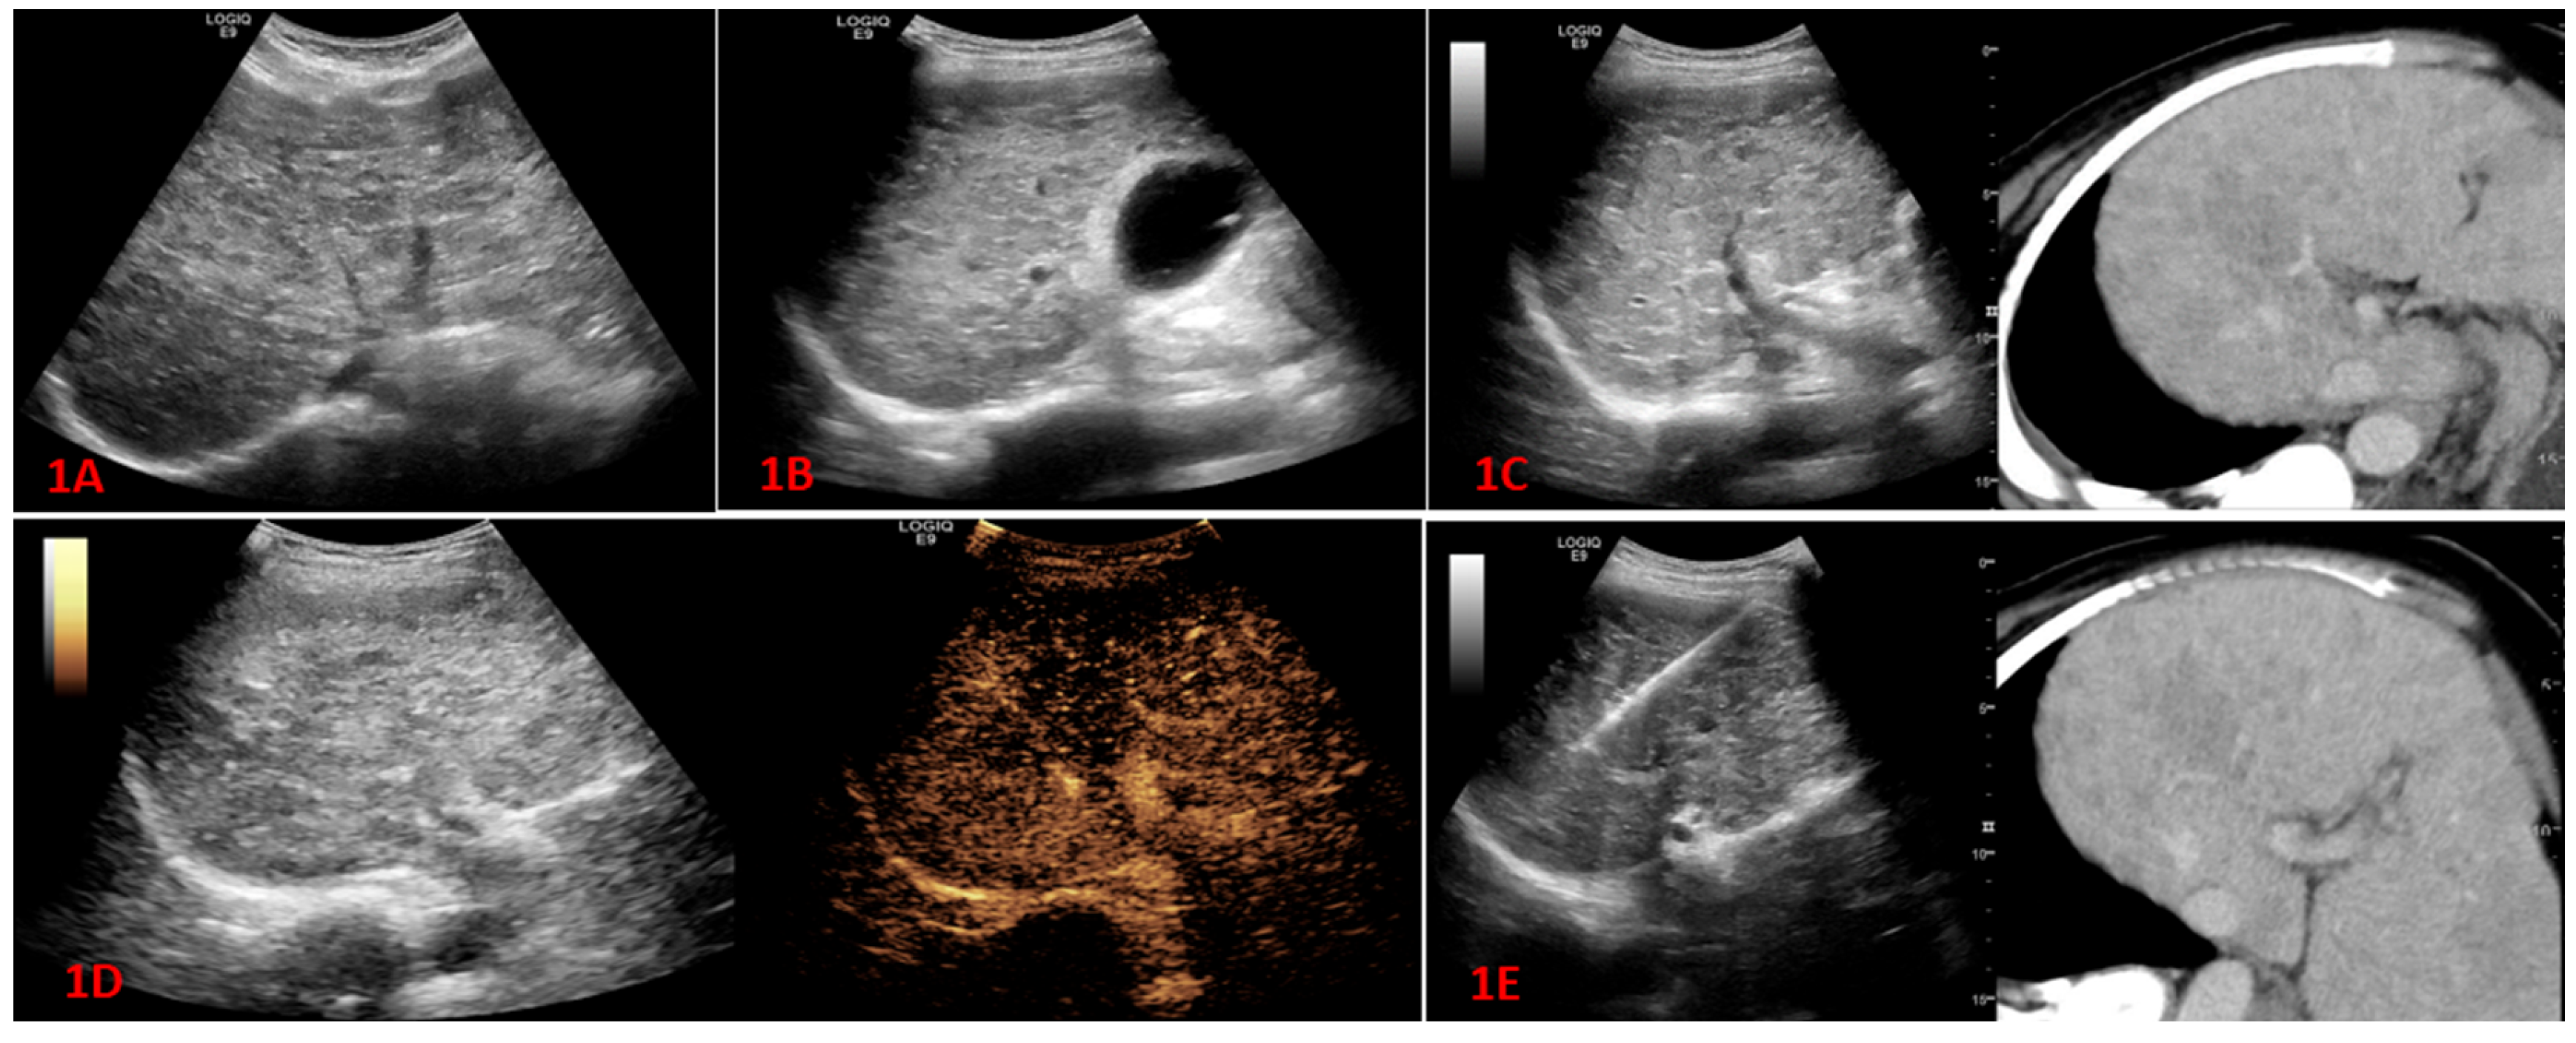

2.2.1. Conventional Ultrasound and Fusion Imaging Methods

2.2.3. Contrast-Enhanced Ultrasound Examination

2.2.4. High-Frequency Contrast-Enhanced Ultrasound Examination